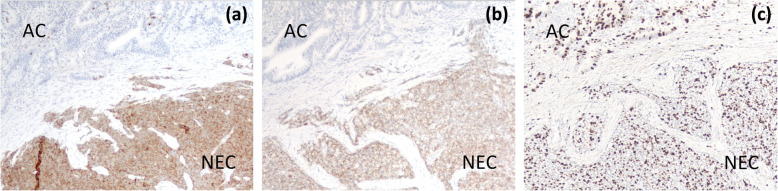

Under a diagnosis of primary cholangiocarcinoma (CCA) of the DBD, a subtotal stomach-preserving pancreaticoduodenectomy was performed. Neither peritoneal dissemination nor lymph node metastases were found during the operation. Macroscopically, an irregularly shaped nodular tumor was found in the DBD (Fig. 4). Microscopically, the lesion was seen to be composed of predominantly well-differentiated tubular AC in the superficial layer of the tumor, admixed with neuroendocrine carcinoma (NEC) in the deeper portion (Fig. 5), indicating a diagnosis of MANEC of the DBD. While the AC component shows papillary growth toward the lumen of the bile duct, the NEC component had infiltrated into the muscle layer, with vascular and neural invasion. Atypical epithelium was found extensively in the superficial epithelium and accessory glands of the CBD, but no malignancies were found in the gallbladder, cholecystic duct, papilla of Vater, pancreas, or duodenum; based on this, the final pathological diagnosis was MANEC of the CBD, Pat Bi, fm, pPanc0, pDu0, pHM0, pEM0, tubular, well-differentiated tubular AC>NEC, INF β, int, ly0, v0, pm1. No lymph node metastases were found. After immunohistochemical staining, NEC components were diffusely positive for synaptophysin and CD56, and the MIB-1 index was 30% (Fig. 6). In both components, p16 was positive and p53 was negative. Additionally, the NEC component was strongly positive for SSTR2, SSTR5, and mammalian target of rapamycin (mTOR) (Fig. 7).

Therefore, to make a correct pathologic diagnosis of MANEC, a surgically resected specimen with immunohistochemical staining for neuroendocrine markers may be essential for the correct diagnosis [ref. 6–ref. 9]. Of the commonly used neuroendocrine markers, two of the most reliable are synaptophysin and chromogranin. Synaptophysin, with its small clear vesicles in tumor cells, and chromogranin, with its large neurosecretory granules, are usually stained diffusely in NEN [ref. 9]. CD56 (NCAM) is also used as a neuroendocrine marker [ref. 21]. In our case, NEC components were diffusely positive for synaptophysin and CD56 on immunohistochemical staining.

The prognosis of biliary MANEC is generally poor. The natural history of these tumors is still under debate with some reporting the NEC component showing more aggressive behavior, whereas others have concluded that, if the NEC component is well-differentiated, prognosis depends on the AC component [ref. 8]. However, the NEC component is said to have a greater effect on prognosis. Zhang et al. [ref. 9] reported significant variation by pathological type in the survival outcome of patients with NEN in the EHBT. The median overall survival for patients diagnosed with NET, NEC, and MANEC was 100, 7.7, and 16.6 months, respectively. Additionally, old age and tumor recurrence were found to negatively affect clinical outcomes. The Ki-67 staining index and mitotic count are crucial for tumor grading, as defined in the classification systems [ref. 11]. Harada et al. [ref. 21] reported that NEC components showed higher proliferative activity on Ki-67 immunostaining, compared to AC components, suggesting that neuroendocrine components, particularly NEC, in biliary MANEC could determine prognosis. In this case, the Ki-67 index of the NEC component was 30%, which was higher than that of the AC component.

The treatment algorithm for MANEC is not well established [ref. 7–ref. 9]. Surgery may be a mainstay for the treatment of MANEC, and adjunctive therapy with chemotherapy, radiotherapy, and somatostatin analogs can be considered according to the NEC type [ref. 7–ref. 9]. The chemotherapy regimen selection for MANEC remains a major clinical dilemma, since it is complicated by a mixture of distinctive malignant histologies. It is reasonable to treat MANEC in accordance with the more aggressive component of the tumor. MANECs containing a well-differentiated NET component and AC component should be treated as ACs. MANECs containing a poorly differentiated NEC component should be treated as NECs. A NEN shown to possess the receptor for somatostatin (SSTR) is a good candidate for treatment with a somatostatin analog. In this case, SSTR2 and mTOR were positive in the NEC component upon immunohistochemical staining, indicating the use of somatostatin analogs as adjuvant therapy. Therefore, after tumor resection, the pathological differentiation and diagnosis of NENs is important for chemotherapy [ref. 21]. Adjuvant therapies have been seldom attempted in patients with biliary MANEC because clear, consensus-based evidence is lacking. However, adjuvant chemotherapy may be justified, as recurrent events were noted in 2/9 patients (22.2%) [ref. 9]. In this case, S-1 was administered 3 months postsurgery as adjuvant chemotherapy because the AC component was dominant in the tumor. Further studies are required to tailor chemotherapy strategies and to determine which component to target to obtain the best therapeutic benefits.